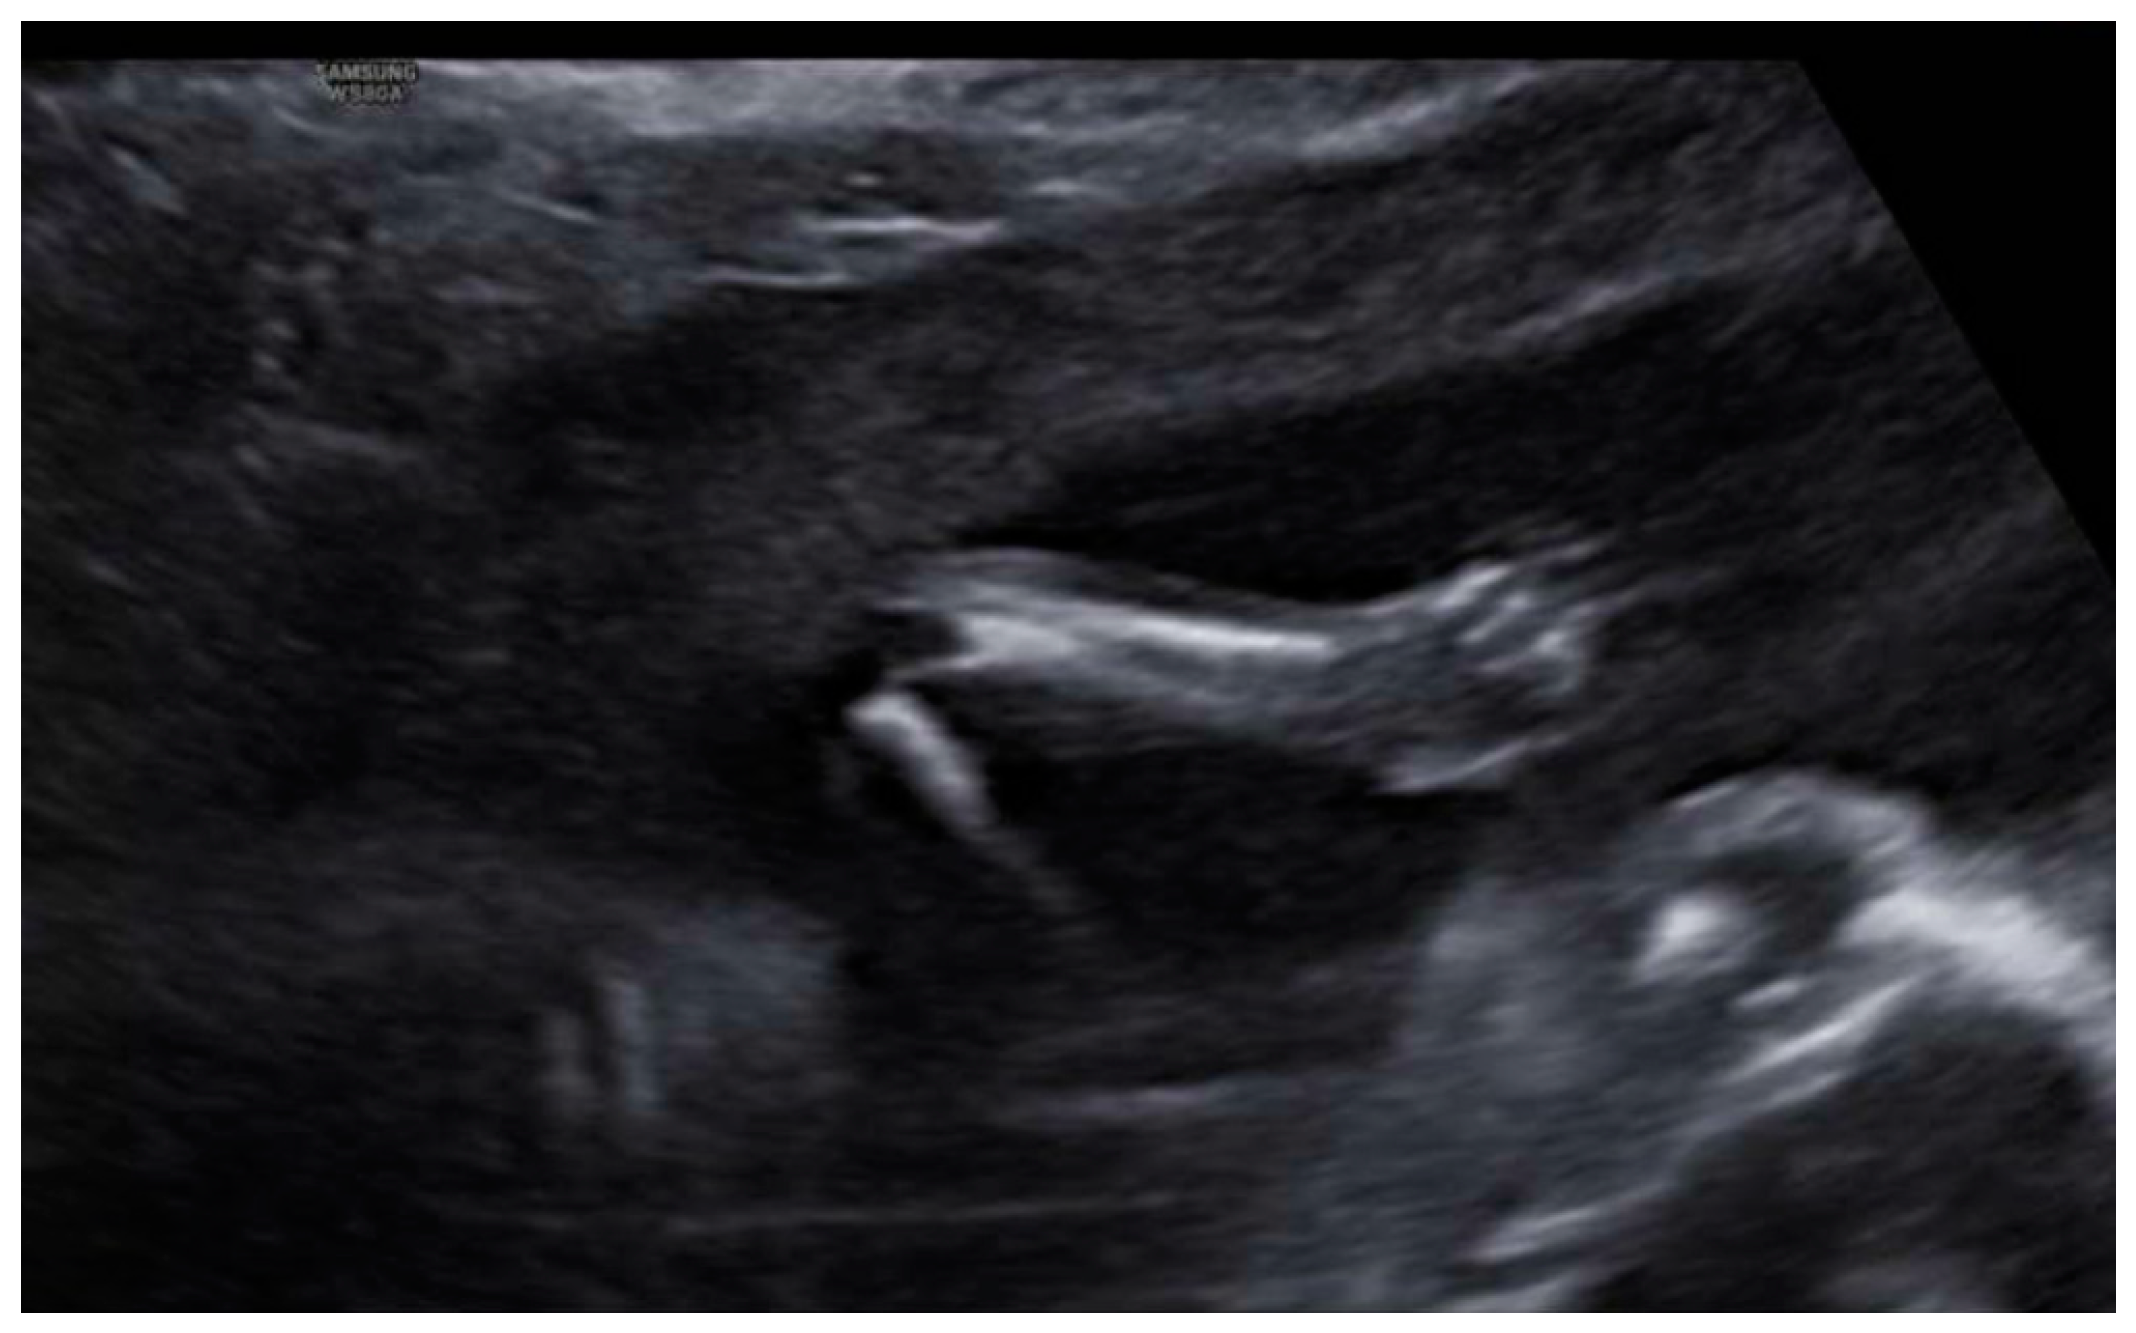

3. Results: Case Presentation